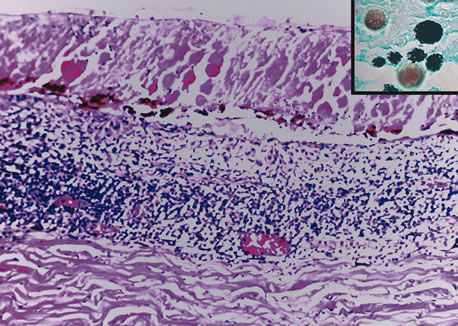

Necrotizing retinitis with secondary choroiditis is seen in protozoal infections such as toxoplasmosis or in herpetic infections. Infection with Toxoplasma gondii leads to retinitis and secondary choroiditis (Fig. 25), usually granulomatous.127 Congenital infection can be acquired in utero by transplacental transmission of the parasite from the infected mother to the fetus.128 Acquired disease occurs after ingestion of oocysts or tissue cysts.129–132 The congenital form of infection leads to atypical macular colobomas. Reactivation of the infection is caused by release of organisms that have remained dormant in the margins of old congenital retinal scars.133 The slowly proliferating form of the organism, termed the bradyzoite, can be seen in cysts. The rapidly multiplying form, termed the tachyzoite, may be difficult to identify in an infected retina or in immunocompetent individuals, but they are frequently seen in the retinitis of immunocompromised hosts.134 Active infection usually causes focal retinal opacification and an intense vitritis. These findings may give the appearance of a “headlight in a fog” in an immunocompetent person. In contrast, this clinical presentation is rare in patients with AIDS, in whom diffuse retinitis is observed with non-granulomatous choroiditis.134

Fig. 25. Toxoplasma retinochoroiditis. Necrotic retina shows cysts of toxoplasma gondii, and the choroid reveals granulomatous inflammation. (Hemotoxylin-eosin ×65.) Inset (Gomori methenamine silver ×160) shows cysts of the organisms.